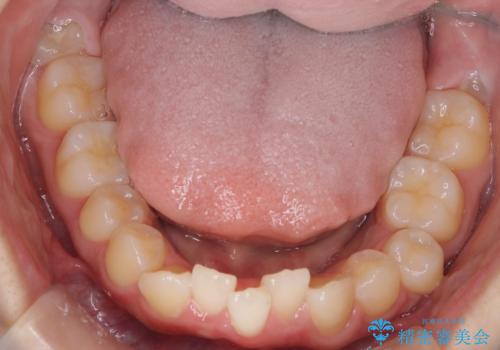

下顎前歯が1本欠損していることもあり、前突はある程度残ることを説明し、インビザラインにて治療を行いました。

下顎前歯が1本少ないため、上下の正中は合いません。